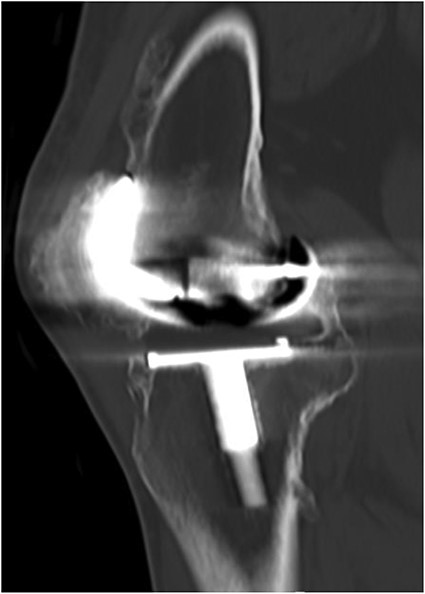

A 32-year-old female known case of rheumatoid arthritis affecting both knees presented to our clinic complaining of severe right knee stiffness post TKA 4-years-ago done in an outside facility (Figs. 1 and 2). She lives in a rural community and was on hydroxychloroquine, but her disease was active as she was not compliant to her medication. On physical examinations, the right knee was larger in size compared to the left knee without joint effusion. Range of motion was zero on flexion, −10° in extension. Standing knee X-ray showed HO around the prosthesis (Fig. 2). Computed tomography (CT) demonstrated extensive HO with implants fixed in place (Fig. 3). Revision surgery and replacement of the prostheses was considered to restore function.

Preoperative standing X-ray showing heterotopic ossification around the prosthesis with preserved knee joint. (A) Heterotopic bone extending proximally on the anterior surface of the femur. (B) Posterior heterotopic bone fusing the knee joint. Careful removal with osteotomes and bone curettes was necessary to remove the old implants.